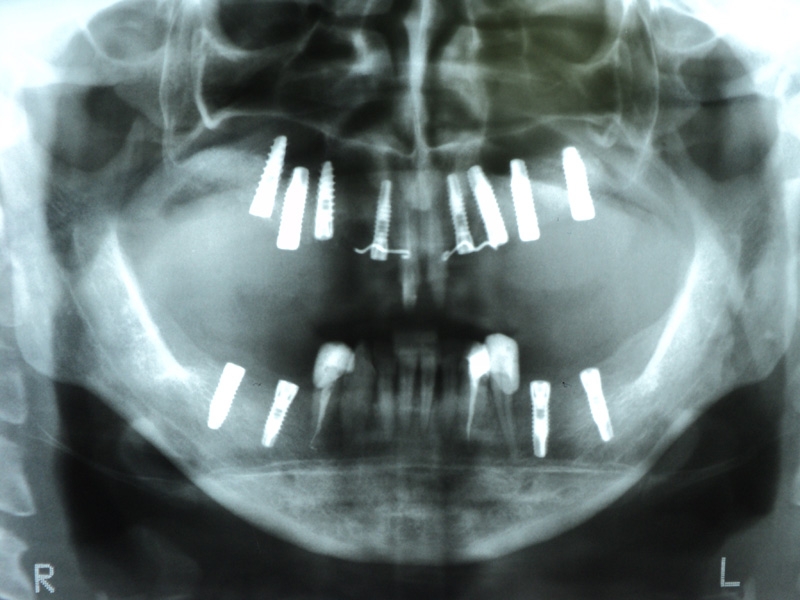

Implante - Galerie Foto

Caz III